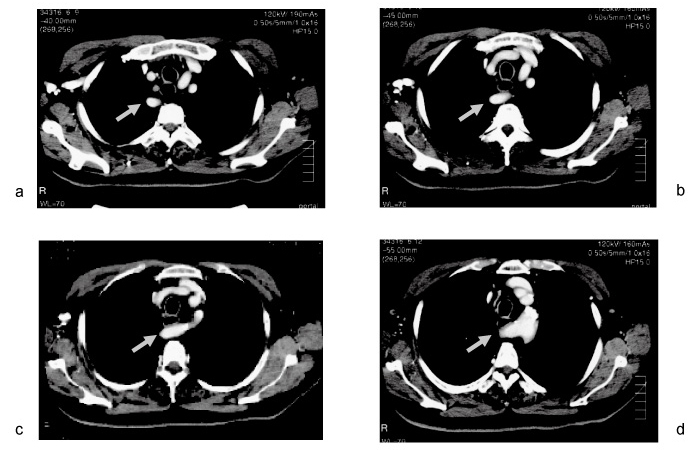

Fig. 2

Enhanced computed tomography showing a right retroesophageal subclavian artery (gray arrow), which arises from the aortic arch as its 4th branch (d), and runs rightwards between the esophagus and the vertebra (c, b) and upwards along the right side of the esophagus (a).